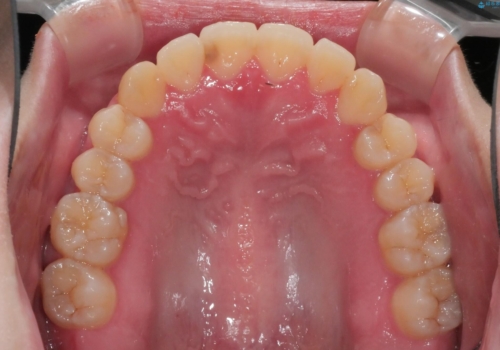

八重歯とクロスバイト:インビザライン治療

- 八重歯が気になるとの事でご相談にいらした方です。

インビザラインで綺麗に並べました。

気になっていた八重歯が綺麗になって大変喜んでいただけました。